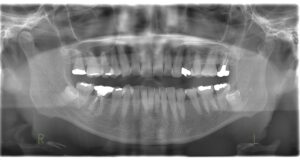

歯ぐきを切除すると共に歯を支える歯槽骨を削って、歯茎を大きく下げるイメージです。歯を長く見せる術式になります。歯肉と骨の両方を削合するので、効果を得やすいですが比較的大きな侵襲がかかります。歯が長く、歯を支える骨が十分にある歯が適応です。ただし今まで口腔内に出ていなかった歯根が口腔内に露出することになるので、知覚過敏のリスクがあります。歯そのものの長さが短いと、歯を支える骨が少なくなり歯が揺れてしまうので、適応症ではありません。

歯冠長延長術とは少し違い、メスで余分な歯ぐきだけを切除し、歯を長く見せます。ですから比較的低侵襲で行えます。歯を支える骨に問題なく、歯肉だけが多い場合が適応です。こちらも、今まで口腔内に出ていなかった歯根が露出するので知覚過敏のリスクがありますが、歯冠長延長術よりも低リスクです。切除量はさほど大きくできないので、効果は限定的です。

簡単に言うと、矯正力を使って前歯を骨の中にめり込ませる治療です。矯正用のインプラントと矯正用のゴムを用いて歯を押し下げます。期間は1〜2年程度が一般的です。この押し下げに用いる矯正力のコントロールが難しいです。また、ご自身でゴムを使ってもらわないといけないです。骨にめり込ませるというのは、指で歯を押し込むように力を加えていただくとわかると思いますが、骨の硬さにもよりますが難しいです。せいぜい1~2㎜くらいだと思ってもらうとよいかと思います。

上顎の外科的骨切り術

上顎の前方への過成長が原因の場合、顎そのものを一部切除して後ろに下げます。顎を後ろに下げますから根本的な改善が可能です。矯正治療で、抜歯をして治療することがあります。犬歯の1本後ろの歯を抜歯することが多いのですが、その歯と骨を切除するというイメージです。自費治療で全身麻酔下での手術となります。また噛み合わせに問題がなければ、上が後ろに下がった分、下顎も下げないといけません。上だけがいわゆる出っ歯であれば上だけで済むこともあります。